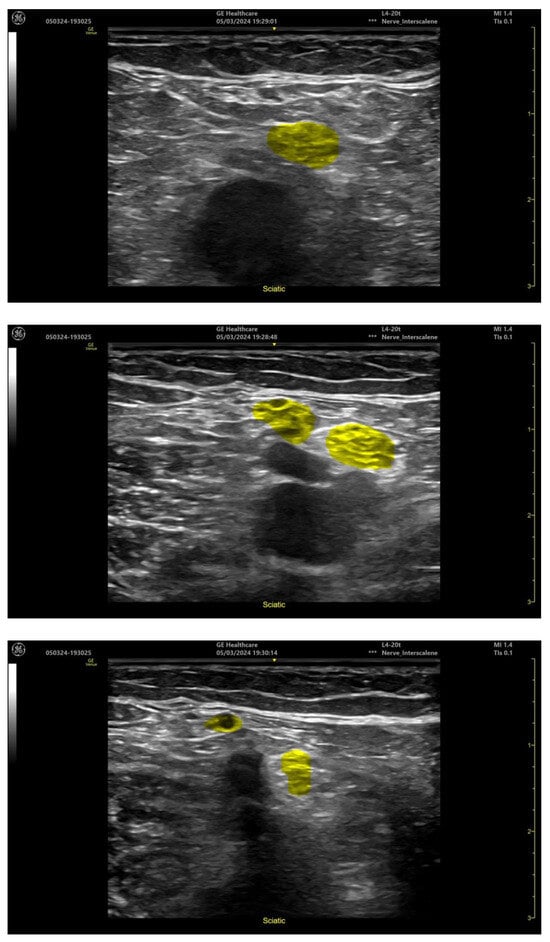

| Popliteal Level Sciatic Nerve | ||

| Popliteal artery | 39/40 (97.5%) | 1/40 (2.5%) |

| Sciatic nerve | 40/40 (100%) | 0/40 (0%) |

| Tibial nerve | 39/39 (100%) | 0/39(0%) |

- Delvaux, B. cNerve, AI to Assist in Ultrasound-Guided Nerve Blocks. Available online: https://www.gehealthcare.com/-/jssmedia/gehc/us/files/products/ultrasound/venue-family/whitepaper-cnerve-pocus-venue-family-jb20312xx.pdf (accessed on 1 January 2024).